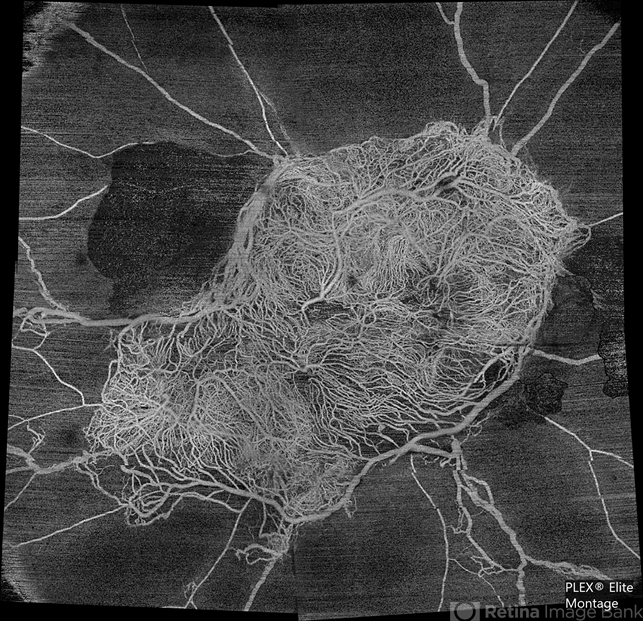

- florid type PDR, OCTA

- Superficial capillary plexus slab montage image of a young female diabetic with florid proliferation . There is no flow in the capillaries anterior to the tangle of new vessels indicating severe retinal ischemia.